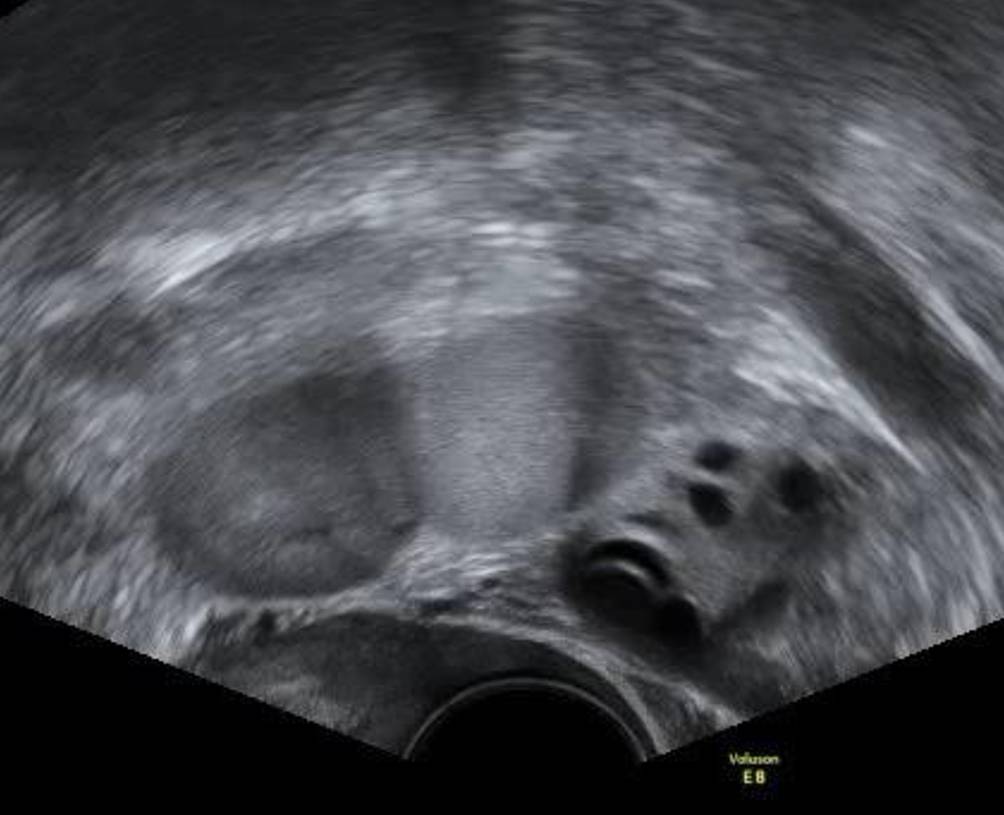

Abb. 4

Seitlich angeschnittene Beckenniere nahe am linken Ovar und den Iliakalgefäßen

Beckennieren sind bei Frauen wesentlich häufiger als bei Männern und häufiger auf der linken als auf der rechten Seite. Meist sind sie den Patientinnen bekannt, sie können aber durchaus auch bei einem Vaginalultraschall erstmals auffallen. Es gibt auch Patientinnen, die abwarten, ob die junge Ärztin oder der Arzt ihre Beckenniere erkennt und etwas dazu sagt. Auch wer routinemäßig Nierenschälle macht, wird eine Beckenniere nicht auf den ersten Blick als solche erkennen: Da im Zuge der embryonalen Entwicklung einer Nierendystopie die Rotation der Nieren selbst gestört ist, liegt das Nierenbecken ventral des Nierenparenchyms und nicht medial (Abb. 3). Die Beckenniere sieht also nicht aus wie eine „typische“ Niere im Ultraschall und kann auf den ersten Blick auch für einen soliden Ovarialtumor gehalten werden (Abb. 4). Steht die Diagnose fest, sollte die Gelegenheit genutzt werden, gleich mit 3‑D-Ultraschall nach einer Uterusfehlbildung zu fahnden, da diese bei Nierendystopien gehäuft auftreten [8].